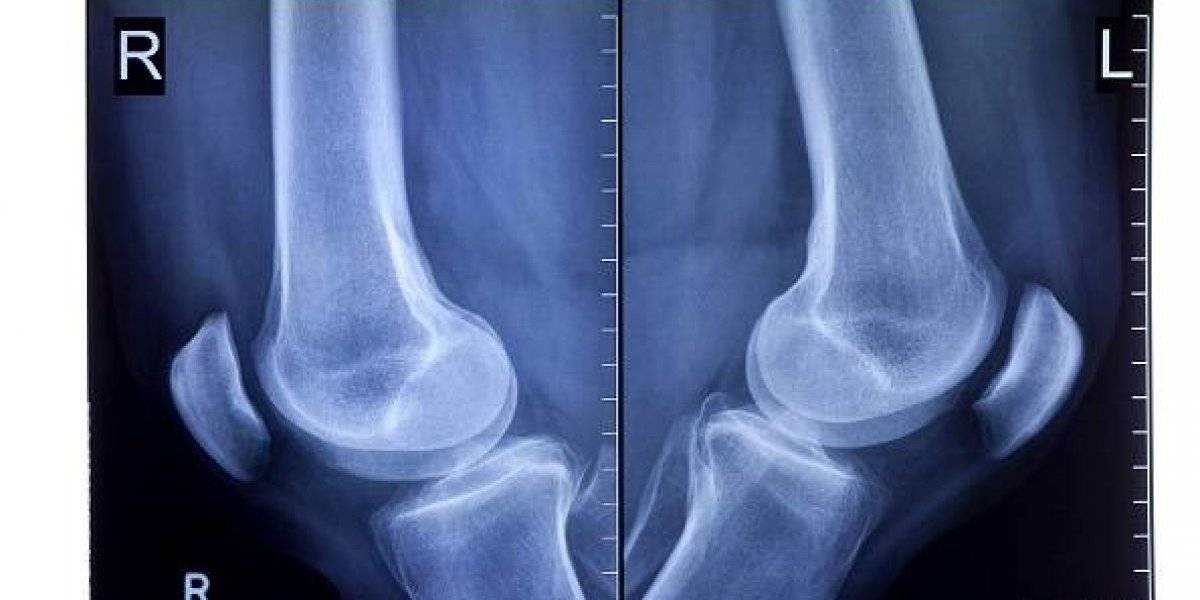

Acorde a una investigación de la Escuela Imperial de Londres, se trata de la fabela, el cual es un pequeño hueso que se encuentra incrustado en un tendón detrás de la rodilla.